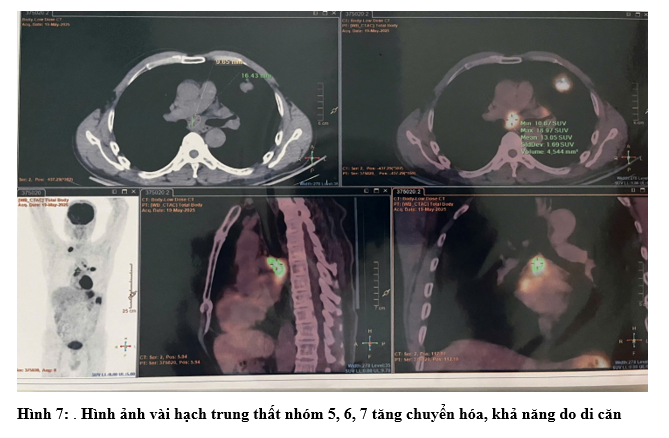

- Chụp PET/CT: Hình ảnh dày thành đại tràng góc lách, dày nhất 18mm, trên đoạn 41mm, tăng chuyển hóa, thâm nhiễm mỡ xung quanh. Vài hạch ở cạnh tổn thương đại tràng, cạnh động mạch chủ bụng và cạnh thân tụy tăng chuyển hóa, khả năng do di căn. Hình ảnh tổn thương bờ tua gai ở S3 phổi trái, kích thước 31x26x22mm, tăng chuyển hóa, khả năng là tổn thương ác tính nguyên phát. Hình ảnh vài hạch trung thất nhóm 5, 6, 7, hạch thượng đòn Phải tăng chuyển hóa, khả năng do di căn. Hình ảnh vài nốt bán đặc và kính mờ rải rác nhu mô phổi 2 bên, có nốt tăng chuyển hóa, khả năng do di căn

- Ung thư đại tràng ngang cT4N1M1 (di căn hạch ổ bụng) - Ung thư thùy trên phổi trái cT4N3M1 (di căn phổi phải, tuyến thượng thận trái)

+ Tại hạch cổ phải: Ung thư biểu mô di căn nguồn gốc tại phổi. EGFR(-)